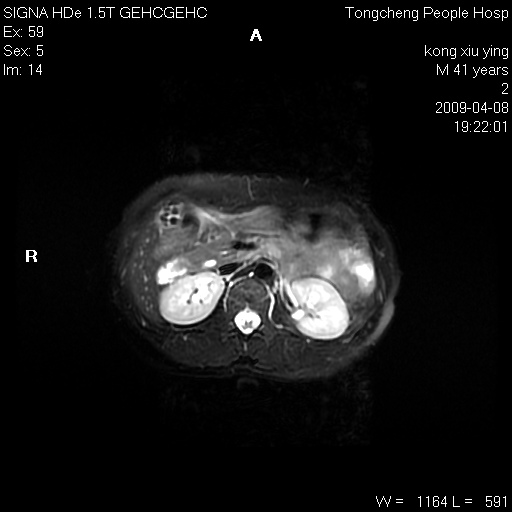

标题: CL1008:【经典】胆囊石榴籽样结石。 [打印本页]

标题: CL1008:【经典】胆囊石榴籽样结石。

女,41岁。健康体检——彩超提示:胆囊显示不清。平素健康,无不适感。

腹部mr扫描及mrcp,图像如下: